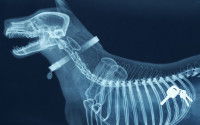

Le vétérinaire commence généralement l’examen du chien par une palpation de l’abdomen, et confirme le diagnostic d’occlusion intestinale par des examens complémentaires d’imagerie (le plus souvent, une radiographie ou une échographie). Dans certains cas, une prise de sang du chien permet de vérifier son état de santé général et les éventuelles conséquences de l’occlusion intestinale.